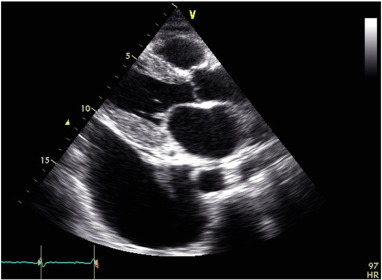

Cardiac amyloidosis results in characteristic changes on echocardiography (see Fig. B.1) [9]; [10]; [11] ;  [12]. These include thickened, speckled ventricular walls (left and right ventricle), small ventricular cavities, dilated atria, thickening of valve leaflet tissue, small pericardial effusions, and advanced diastolic dysfunction. Global longitudinal strain as a more subtle measure of ventricular function may show early changes. Apical sparing strain patterns are thought to be pathognomonic in cardiac amyloidosis [9]; [10]; [11]; [12] ;  [13]. Cardiac magnetic resonance imaging (CMR) demonstrates diffuse circumferential subendocardial, mid-wall to transmural enhancement in a non-vascular distribution in the acute phases of the disease [14]; [15]; [16] ;  [17]. These changes make CMR an excellent tool for the detection of cardiac amyloidosis with high sensitivity and specificity [14]; [15]; [16] ;  [17].

Echocardiography suggested statistically significant regression in the cardiac amyloid process, similar to what had previously been reported [18]. Wall thickness significantly reduced, atrial size shrunk, and measures of diastolic function improved (see Fig. B.1 ;  Fig. B.2). The ejection fraction did not significantly change. Myocardial strain analysis at late follow-up suggested better global longitudinal strain in this highly selected group of survivors, than many cardiac amyloid studies have suggested (the global longitudinal strain was more negative than previously reported for cardiac amyloid patients) [13]; [25] ;  [26]. The mean global longitudinal strain was − 16%. The classical bulls-eye pattern of cardiac amyloidosis was only seen in 50% of these patients [13] ;  [26] (see Fig. B.3 and Table A.2). Strain had not been assessed before PBSCT for any of the patients in this study.

Fig. B.1.

Pre-PBSCT echocardiogram.